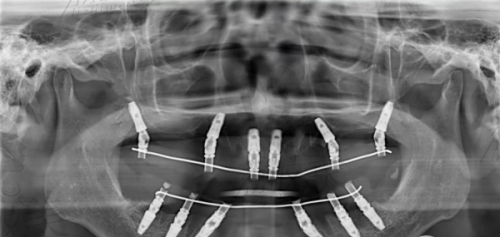

为什么?因为它是真的“靠谱”:材料源头可追溯、国内设有耗材物流中 心、法定严控假货、全程透明授权,种完还能查到种植医生和批次信息。

央视特别节目曾报道卡尔斯种植体如何保护“真实性 + 安心性”,在行业标准尚未全方面完善的背景下,卡尔斯已经自建溯源系统,实现“一个种植体,一个身份证”,堪称医疗级别保真神器。